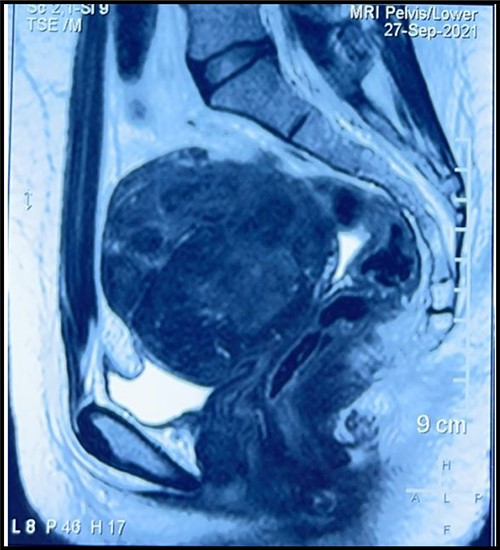

A 28-year-old nulligravida presented to the emergency with urinary retention and abdominal pain for 2 days. She had primary amenorrhea for which workup was done at age of 16 years and diagnosis of MRKH syndrome was made. She got married at age of 20 years and was sexually active since then. She was catheterized in emergency and 2 liters of urine was drained. On examination huge abdomino-pelvic mass of around 20 weeks, nodular, hard in consistency could be palpated. Vaginal length was 7 cm with no history of sexual dissatisfaction or vaginoplasty. Magnetic resonance imaging (MRI) suggested multiple leiomyomas arising for both uterine rudimentary horns (Fig. 1). lntra-operatively, 10 × 9 × 8 cm bilobed hard myoma arising from right uterine horn with one of the lobe deeply embedded in lateral pelvic wall seen and left uterine horn seen to be harboring multiple small fibroids. Both tubes and ovaries were normal. Leiomyoma was removed by traction and countertraction and keeping ureters under vision (Fig. 2A–C). Bilateral rudimentary uterine horns along with median raphe were excised and removed to prevent recurrence (Fig. 2D and E). Post-operative period was uneventful. Histopathology report was suggestive of leiomyoma and rudimentary uterine tissue.